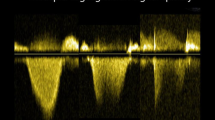

All patients underwent a standard echocardiogram in keeping with current guidelines [11] employing a Vivid E9 ultrasound system (GE Ultrasound, Horten. Norway) equipped with a 2.5 MHz matrix array transducer. 2D gray-scale images were acquired at 50–80 frames/s over three heart cycles. Doppler tracings were recorded using a sweep speed of 100 mm/s. All images were subsequently exported and analyzed offline (EchoPAC PC, version 11.0.0.0 GE Ultrasound, Waukesha, Wisconsin) by experienced operators blinded to catheterization data. Left ventricular ejection fraction (LVEF) was estimated using the Simpson’s biplane method. PVRDoppler were calculated employing four different methods as previously described [5,6,7,8]. To estimate PVRDoppler in the two methods proposed by Abbas et al. [5, 6], peak tricuspid regurgitation velocity (TRVmax) was measured considering the most optimal signal obtained using apical and parasternal windows and right ventricular outflow tract velocity time index (RVOTVTI) was obtained by placing a 5 mm pulse-wave (PW) Doppler sample volume proximal to the pulmonary valve in the right ventricular outflow tract (RVOT) and tracing the resultant spectral wave form. For the method proposed by Scapellato et al. [7], pre-ejection period (PEP) was defined as time between QRS-start and RVOT-onset. Acceleration time (AcT) was expressed as the time between RVOT-onset and the RVOT-peak while total time (TT) was expressed as time interval between RVOT-onset and the RVOT-end. Finally, to estimate PVR using the method proposed by Haddad et al. RVOTVTI was measured as previously described, systolic pulmonary artery pressure (SPAP) was obtained by adding the recommended estimates of RA pressure [11] to the corresponding pressure gradient obtained from the TRVmax signal.

PVRDoppler ability to distinguish PH phenotypes

PVRDoppler by methods proposed by Abbas et al. [5, 6] and Haddad et al. [8] demonstrated a fair discriminatory ability to distinguish Ipc-PH from Cpc-PH subjects in our patient group (Table 5). Of these three, the revised method proposed by Abbas et al. [6] demonstrated highest area under the curve (AUC = 0.79; 95% CI 0.63–0.96; p = 0.001) (Table 5 and Fig. 2a). A cut-off value of 0.59 provided best balanced sensitivity (81%) and specificity (65%) to determine PVR > 3WU. Bland–Altman analysis, however, revealed wide limits of agreement between RHC and Doppler-based PVR (bias = 0; SD = 1.83WU) and greater variability was observed with higher PVR (Fig. 2b). Further, when the difference between PVRDoppler and PVRRHC was expressed as percentage and plotted against PVRRHC, a large relative difference was observed in the setting of non-elevated PVR (Fig. 2c). In patients with PVR ≤ 3WU, Bland–Altman demonstrated better limits of agreement but greater bias with Doppler-based PVR demonstrating higher values as compared with invasive measurements (Bias = 0.8; SD = 0.76WU). No significant difference was observed when comparing AUC curves between PVRDoppler methods proposed by Abbas et al. [5, 6] and Haddad et al. [8] (p > 0.05 for all comparisons).

Diagnostic accuracy of Doppler-derived PVR as per method proposed by Abbas et al. a Receiver-operating characteristic curve. A TRV 2max /TVIRVOT cut-off value of 0.59 provided best balanced sensitivity (81%) and specificity (65%) to determine PVR > 3WU. b Bland–Altman analysis of PVR obtained by Doppler and invasive PVR. c Percentage difference between Doppler-derived and invasive PVR plotted against invasive PVR